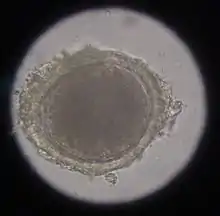

In the case of worms in vomit, the diagnosis can already be made without special examinations. A roundworm infestation can be detected with relative certainty by microscopic detection of the eggs extracted from the feces using the flotation method.

Infection with hookworms often remains asymptomatic in cats. In more severe infestations, they can cause emaciation, anemia or diarrhea. As with roundworms, the infection is detected by detecting the eggs in the feces using a flotation method. They are oval, smaller than roundworm eggs (about 60×40 µm in size) and furrowed stages are already visible inside when the eggs are laid.

In the same animal, usually only two to ten cat tapeworms are found, and they excrete about four to five limbs daily. These elongated trapezoidal structures may already be visible to the naked eye in the anal region. The coated oncospheres, which are about 35 µm in size, can be detected in the feces using flotation methods. In one study, an infestation rate of 25.9% was determined in autopsies, of which only 10% were detected by flotation and 27% by centrifugation.[10] In addition, the eggs cannot be distinguished morphologically from those of other members of the taeniidae (including the fox tapeworm).